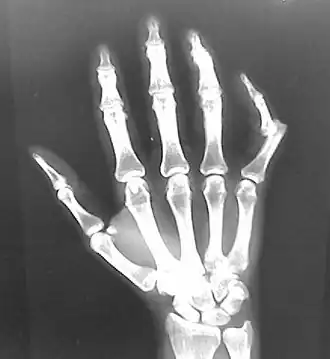

-

Dislocation of the left index finger -

Radiograph of right fifth phalanx bone dislocation -

Radiograph of left index finger dislocation